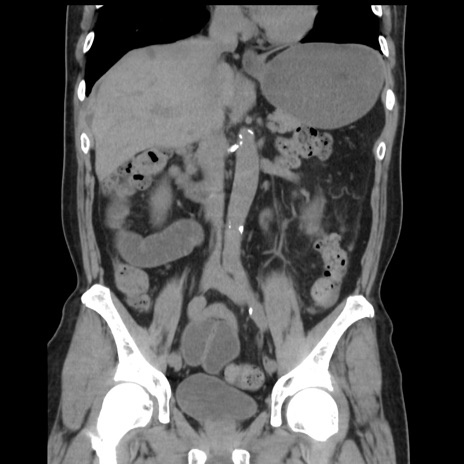

症例16(冠状断像)

【症例】 70歳代男性

【主訴】 腹痛、嘔吐

【現病歴】 約1ヶ月前より間欠的に腹痛と嘔吐あり、当院消化器内科を受診したところCTで多発する肝臓のLDAを指摘され、精査中であった。以降は消化器症状は安定していたが、2日前より嘔気と腹痛があり、同日より排便・排ガスが消失した。改善認めず、 本日、救急外来を受診した。

【既往歴】 大腸ポリープ切除後。

【身体所見】意識清明・会話良好、BT 36.3℃、BP 127/80mmHg、 P 80bpm、腹部:膨満あり、平坦・軟、上腹部正中および下腹部正中に圧痛あり、反跳痛なし、筋性防御なし。

【データ】WBC 7200、CRP 0.77